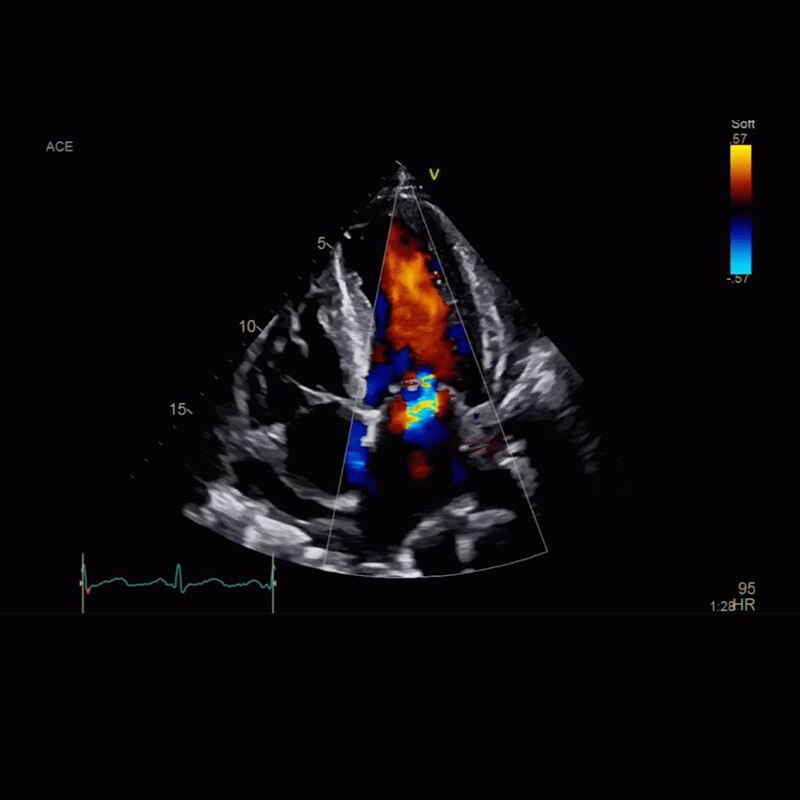

PCI ASSIST13

帮助规划、评估和指导介入手术,在移动解剖学中可视性提高达 85%。了解更多信息

成功的狭窄新病变 PCI 包括对罪犯病变的规划、指导和评估,以及对冠状动脉其余部分的评估。

PCI ASSIST6

帮助规划、评估和指导介入手术,在移动解剖学中可视性提高达 85%。